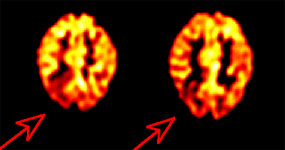

BGO versus LSO detector: The images below were acquired in 2D mode with a scan time of 5 min/bed emission and 3 min/bed transmission. The upper row of images were acquired on a BGO camera system and the lower row of images were acquired on a ECAT Accel LSO PET camera system. The data was reconstructed using normalized attenuation weighted OS-EM reconstruction. Image courtesy of Northern California PET Imaging Center, Sactamento, CA and CTI, The Power Behind PET. |